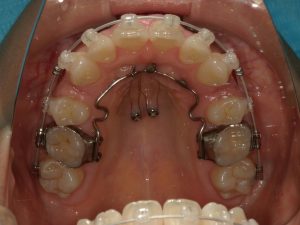

- 主な使用装置

- マルチブラケット装置(+ホワイトワイヤー)、リンガルアーチ、アンカースクリュー

治療中の様子(アンカースクリュー)